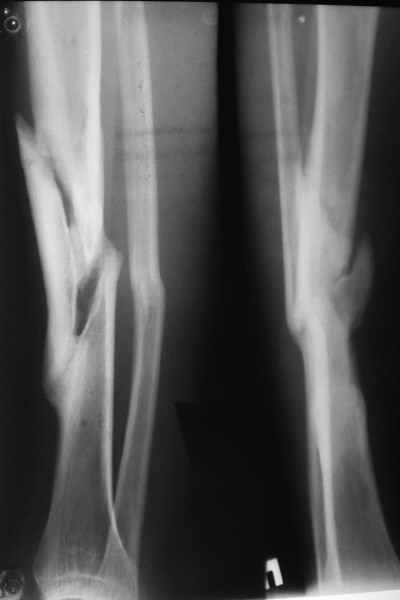

Уважаемые коллеги! На консультации больной предъявляет жалобы на хромоту (укорочение - 2см), боль в месте перелома при нагрузке (спортсмен).

Семь месяцев назад получил закрытый перелом, лечился консервативно в одной из больниц города. Как-бы кто лечил? Сам склоняюсь к LCP с костной пластикой.

Юрий Алексеевич, привет. А перелом то вроде сросся! -правда с варусом - угол можно посчитать у Вас по снимкам (в письме - суставов нет в прямой проекции). Я бы не спешил, с открытой хирургией тем более. Риски велики. Укорочение абсолютное тоже мизерно. А коррекцию оси сделал бы попозже малоинвазивным методом по Илизарову ГА.